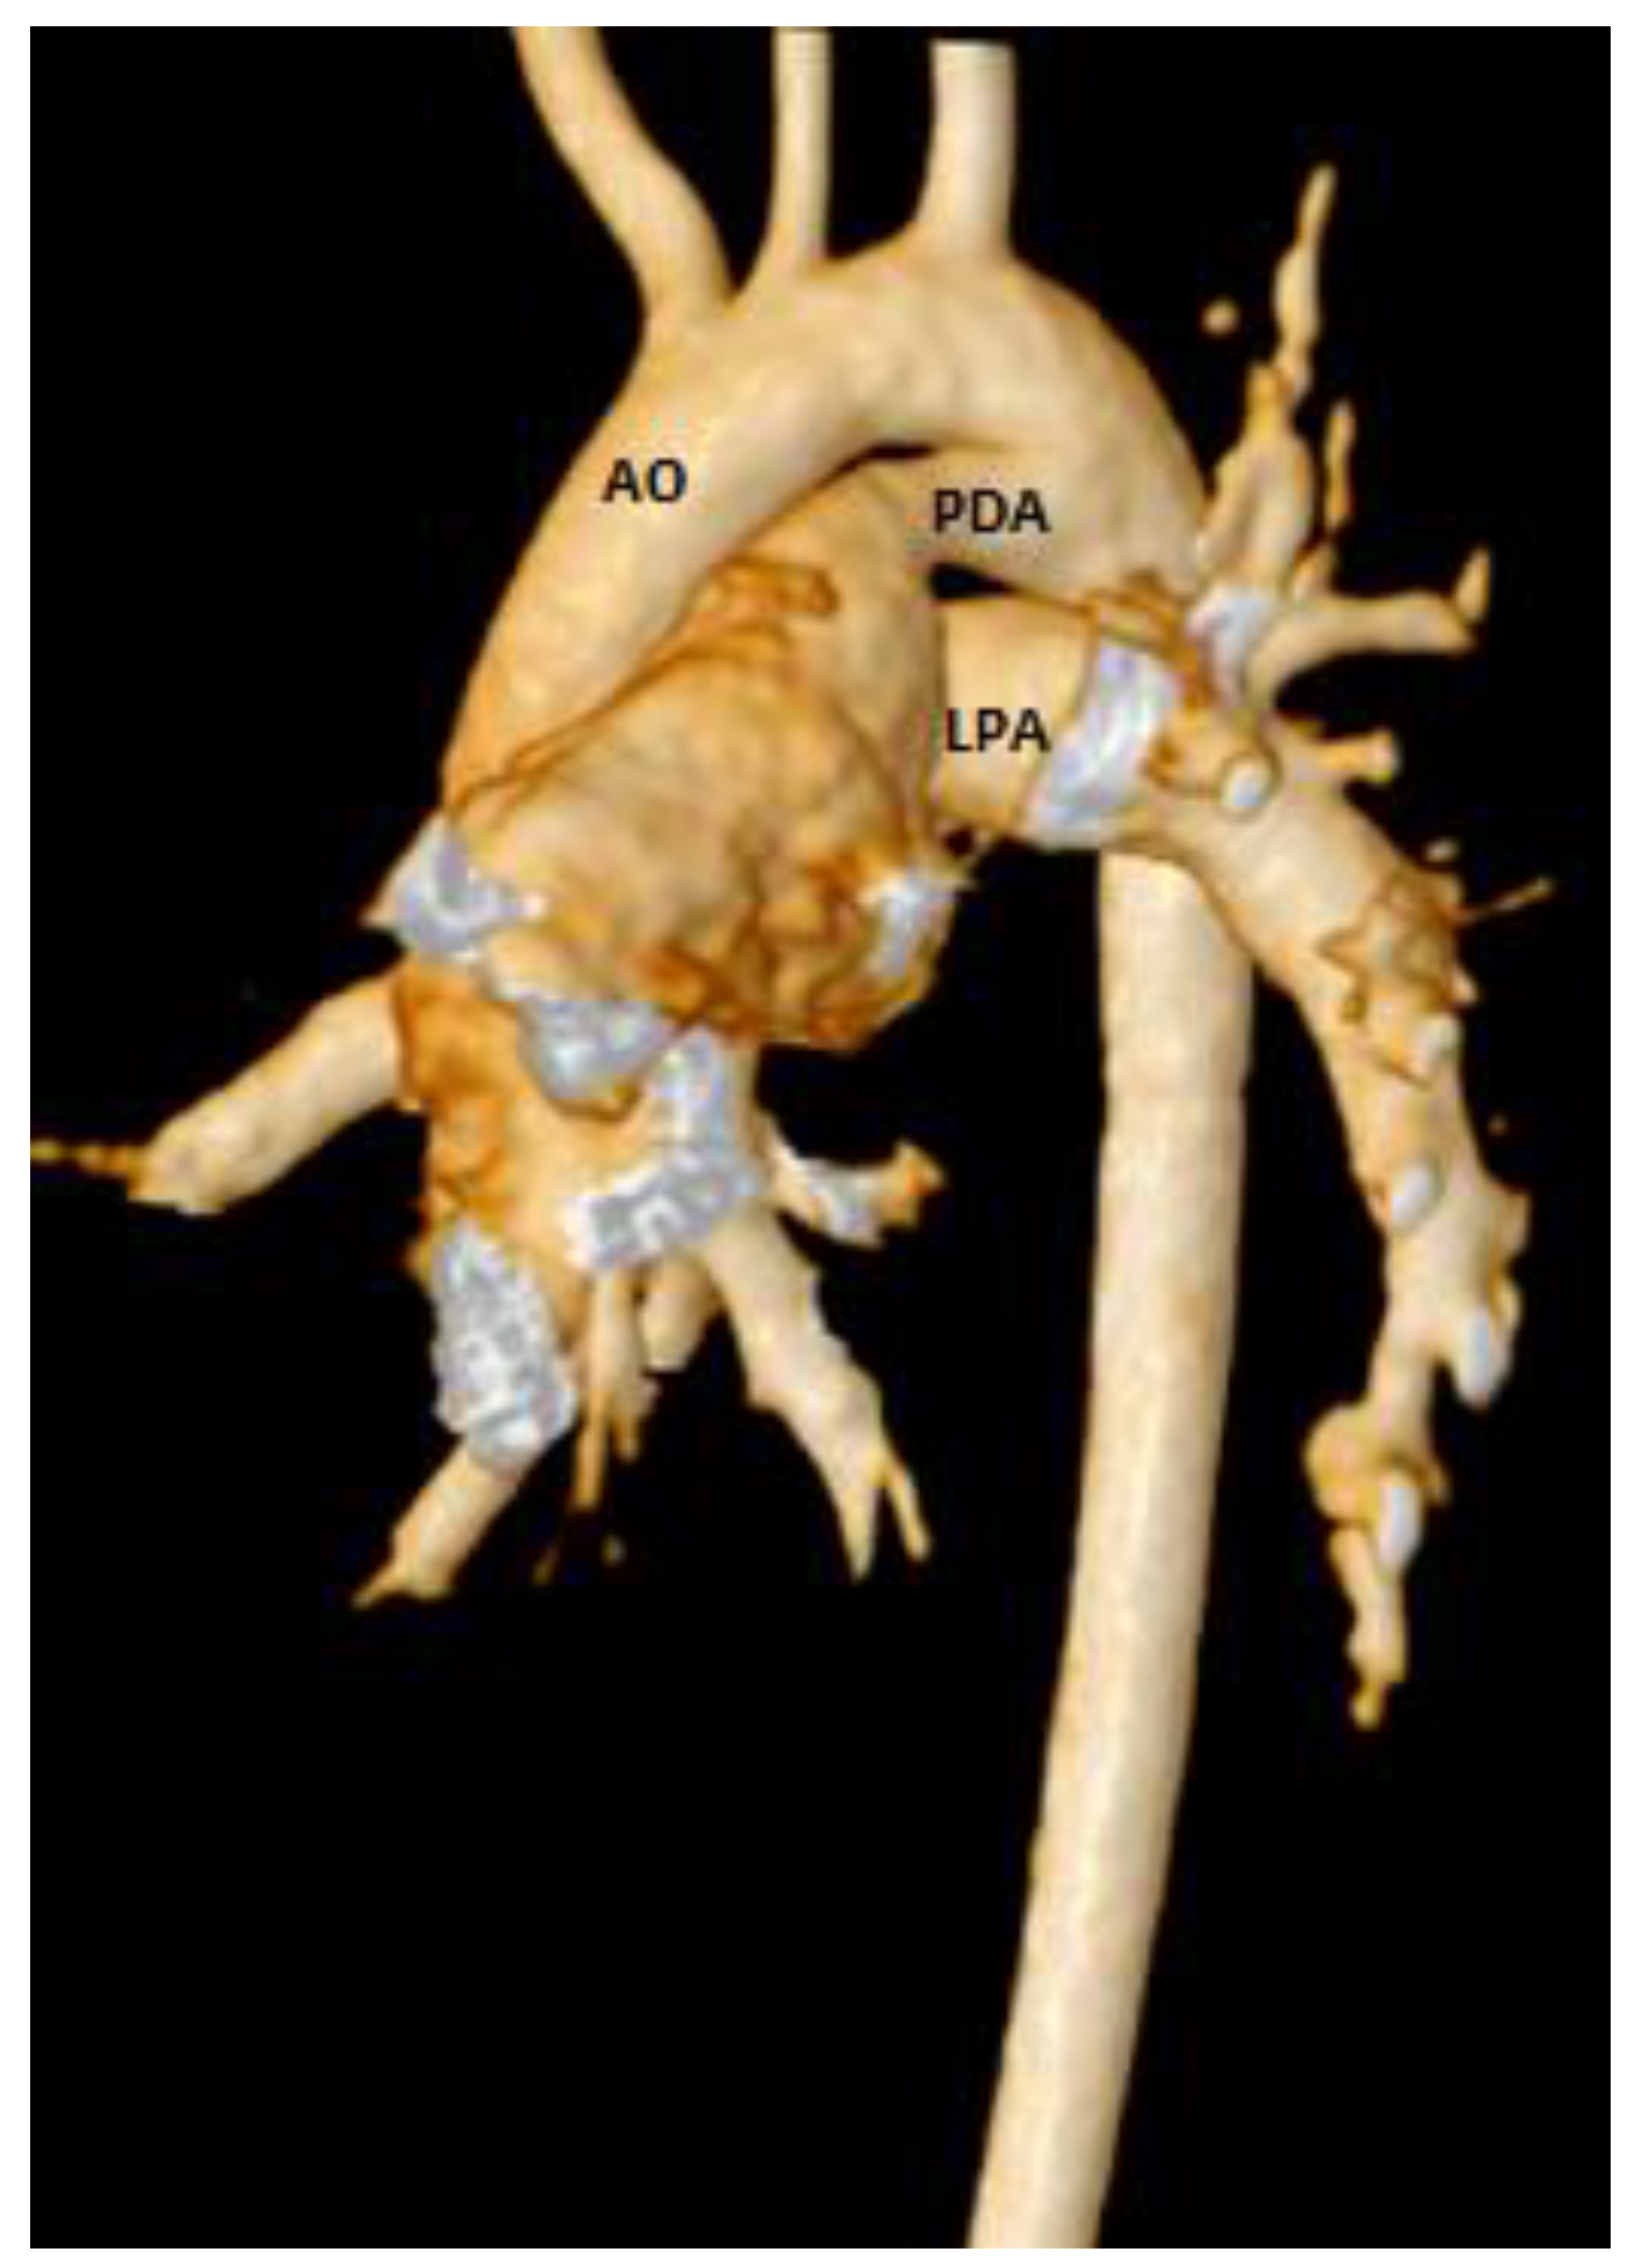

Total pulmonary blood flow assessment was done by summing the flow in the right pulmonary artery (RPA) and the left pulmonary artery (LPA) distal to PDA entrance, the approach based on the assumption that total pulmonary flow can be more accurately quantified by measuring flow in each branch artery [9]. Cardiac output was calculated by measuring blood flow in the ascending aorta as previously described [10]. The total pulmonary blood flow was calculated using the measured RPA and LPA net antegrade blood flow volume [11]. A 6 French balloon wedge catheter was used to perform the CMR-guided RHC procedure. Using the Philips interactive scanning mode guidance (Philips Healthcare), the interventionalist advanced the gadolinium-filled balloon tip of the wedge catheter and MR-conditional guidewire (Emeryglide MRWire Nano4Imaging, Aachen, Germany) (Figure 4). Magnetic resonance imaging provided excellent soft-tissue contrast for completing the right heart catheterization, including 3D reconstruction of the aortic arch, PDA, and branch pulmonary arteries (Figure 5).

Figure 5.

3D CMR reconstruction showing the aortic arch (AO), patent ductus arteriosus (PDA), and left branch pulmonary artery (LPA).